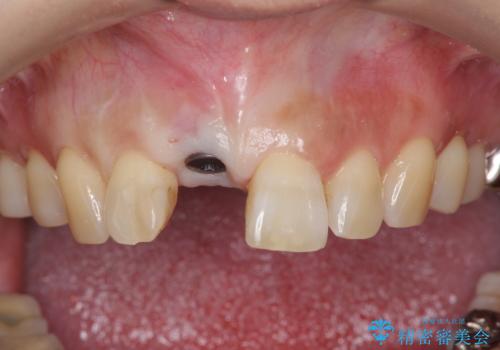

骨造成を伴う前歯のインプラント治療

- 前歯を外傷により失い、審美性の改善を求めて来院されました。

横の歯を削る必要のあるブリッジ治療、着脱の必要な入れ歯に強い抵抗があったためインプラント治療を計画します。

審美的・機能的に良好な位置に埋入するには、骨量が十分ではなかったため骨の造成を併用したインプラント埋入外科手術を行います。

前歯のインプラントを審美的に仕上げるには、インプラント周囲に十分な骨の量と厚みのある歯肉、そして埋入位置の精密な位置付けが重要です。